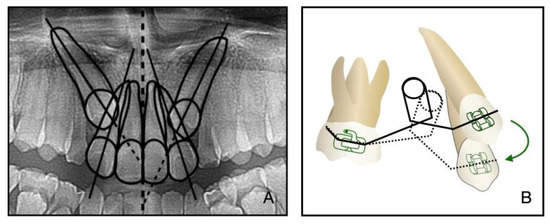

2.4. Treatment Progress

In addition to the maxilla-mandible relationship, the arch and the dentition play an important role in long-term stability. The etiology of the impacted teeth was related to the arch-length deficiency, which occurs in hypo-developed maxilla and may lead to bilateral impacted canines, which happened in this case. A treatment alternative is extraction; however, after extraction, there is a need to figure out an approach to replace the pivotal esthetic and the occlusion function of the missing canines, such as implant-retained crown restoration, conventional bridge, or premolar substitution through orthodontic treatment. The panoramic radiograph showed the canine crown was in the buccal side and distal to the midline of the lateral incisor, which noted a higher rate of successful traction, even up to 91% [3]. However, it takes space to decompensate and tract maxillary anterior teeth, so the extraction project was beneficial to create space [14]. Meanwhile, extraction guided the posterior dental arch to move relatively forward, which was equivalent to increasing the arch of the upper jaw and conducive to the establishment of a normal overjet and overbite of the posterior teeth. All things considered, a removal of the deciduous canines and the first premolars was decided, and then surgical exposure and a segmental arch technique were performed to tract the canines (Figure 12). The pre-surgical planning was mainly to tract the impacted teeth and create enough overjet and overbite for jaw movement, which was established a stable jaw–tooth relationship and improved the profile. The pre-surgical treatment went on for 2 years to achieve the traction of canines and reach the proper timing for the orthognathic surgery, which seemed longer compared to routine cases. Finally, we placed the canines correctly and established an ideal occlusion. Proper overjet and overbite, coordinate width, and close occlusion helped maintain the stable dentition relationship and further ensured the stability of the jaw’s position and soft tissue aesthetic.

Figure 4. Tracting the impacted maxillary permanent canines with the segmental arch technique.

Figure 12. (A): The relative position of the canine crown and lateral incisor in a panoramic radiograph. (B): Biomechanism of canine traction through segmental arch. The green arrow illustrates the path of canine movement.